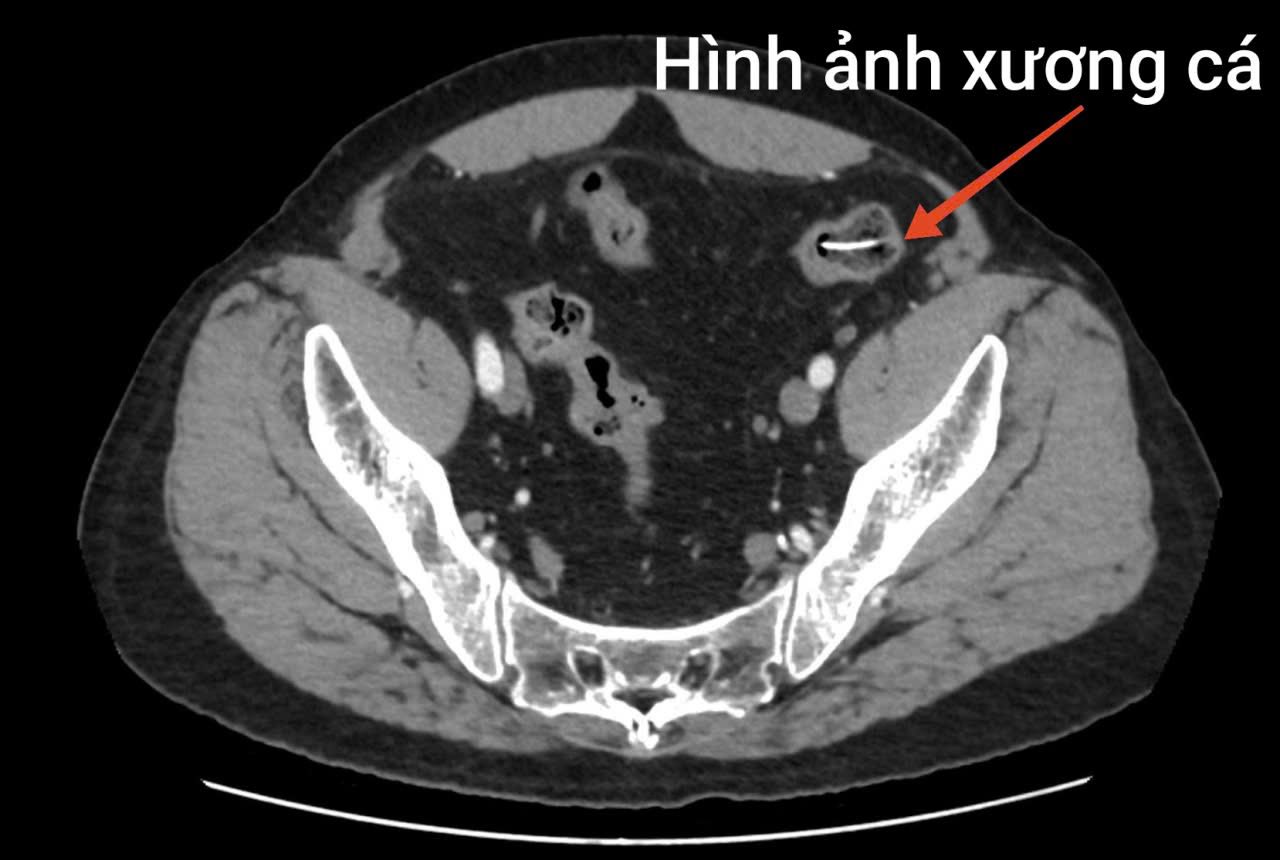

Kết quả xét nghiệm và chẩn đoán hình ảnh cho thấy tình trạng nguy hiểm của bệnh nhân: chỉ số bạch cầu tăng cao (14.6 10^9/L), hình ảnh nhiều dị vật hình xương cá nằm ngang đoạn ruột non. Kèm theo vị trí đại tràng xuống vùng hố chậu phải trong lòng có một dải tăng tỷ trọng (kích thước 24 x 6mm). Bệnh nhân được chẩn đoán thủng ruột non do dị vật, với bệnh nền bệnh phổi tắc nghẽn mạn tính và được chỉ định phẫu thuật cấp cứu.

Trong quá trình mổ, ê kíp phẫu thuật phát hiện ổ bụng bẩn nặng, nhiều giả mạc, dịch ổ bụng đục, tập trung ở hạ vị – hố chậu phải. Tại vị trí ruột non cách góc hồi manh tràng khoảng 1 mét, có dị vật hình xương cá dài khoảng 4cm chọc thủng ruột non tạo thành 01 lỗ thủng đường kính khoảng 0,5cm.